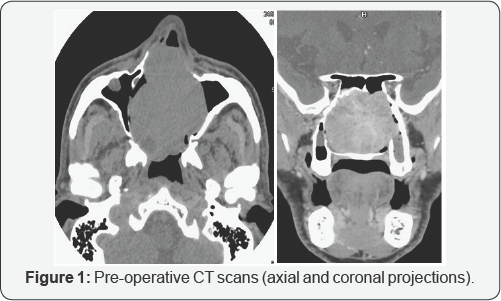

The control computed tomography with mean of contrast showed the hyper vascular fleshy mass with a volumetric increase (49 x 59 x 49mm) with respect to the previous exam. It had a multilobed aspect with the involvement of the whole nasal cavity, both ethmoidal labyrinths, both maxillary sinuses, the left frontal sinus and the sphenoid right one. The left lacrimal sac and the corresponding nasolacrimal duct appeared infiltrated, with a bilateral thinning of the lamina papyracea (Figure 1). A conventional angiography was performed to confirm the vascular nature of the tumor: a pathological flow from the branches of the internal maxillary artery and from the anterior and posterior ethmoidal arteries was noticed (Figure 2). A complete tumor embolization was performed with super selective catheterization of the internal maxillary artery with coaxial Rapid Transit® system, using four vials of 10 ml each of 500 micron microspheres. Np embolization of the ethmoidal arteries was carried out to avoid any risk of sight impairment.

Pre-operative examinations must include neuroradiological investigation to detect the vascular nature of the tumor and its extension. CT scans of the nose and paranasal sinuses can demonstrate bone involvement, and the intravenous mean of contrast infusion can show tumor enahancement, but it does not allow a clear distinction with inflammatory fluid [14]. Usually, MRI scan shows a solid isointense mass, with a strong enhancement after gadolinium on T1 weighted sequences. On T2 weighted imaging, HPCs appear isointense to low intense, while inflammatory fluids have high-intense signals [12]. The best visualization of the vessel supply of the SNTHPC can be achieved by conventional digital angiography, which helps at the same time to plan a preoperative embolization [15].